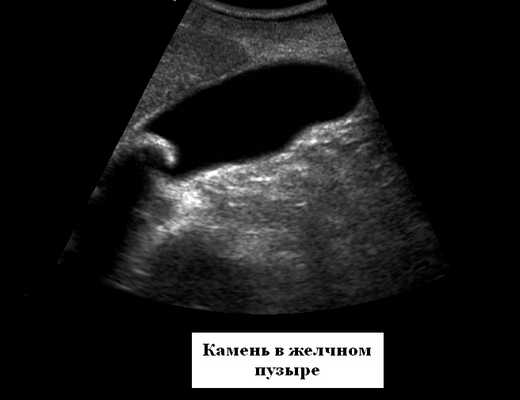

1. Со стороны желчного пузыря:

- острый и хронический холецистит

- эмпиема пузыря

- желчно-каменная патология

Желчный пузырь

Норма УЗИ по результатам осмотра этого органа:

- Форма: различная - грушевидная, цилиндрическая.

- Размеры: ширина 3-5 см, длина 6-10 см.

- Объем: 30-70 куб. см.

- Стенки: толщиной до 4 мм.

- Образования в просвете: в норме их нет.

- Акустическую тень от образований: это касается камней и опухолей пузыря. По наличию этой тени проводится расшифровка видов камней (они бывают разного состава).

- Смещаются они или нет: камни обычно подвижны, но могут быть припаяны к стенке или иметь крупные размеры. По этому и некоторым другим признакам можно судить о том, не является ли образование опухолью.

Признаки патологии желчного пузыря

- При остром холецистите отмечается утолщение стенки органа, при этом размеры могут быть нормальными, уменьшенными или увеличенными. Стенка может быть также описана как «двойной контур», а наличие жидкости вокруг пузыря говорит о том, что уже развился местный перитонит, и нужна срочная операция.

- Утолщение стенки будет и при хроническом холецистите. Контур в этом случае четкий и плотный.

- В заключении могут быть описаны различные деформации органа. Это - не заболевание, а особенности строения.

- Если описаны эхонегативные объекты, которые оставляют акустическую тень, при этом стенка пузыря утолщена, а контур неровен, речь идет о калькулезном холецистите. При этом расширение желчных протоков говорит о том, что камень перекрывает выход желчи.